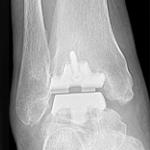

足の外科

Foot and Ankle

聖マリアンナ医科大学科学講座の足の外科の歴史は故三好邦達初代主任教授の時代から始まります。三好教授は先天性内反足をはじめとする足の外科領域の診療、研究に力を注ぎ「日本足の外科研究会」を発足されました。昭和51年に第1回の会長を務められ、その後に名称を「日本足の外科学会・学術集会」とし平成9年に青木治人第2代主任教授が第22回を開催されました。・・・